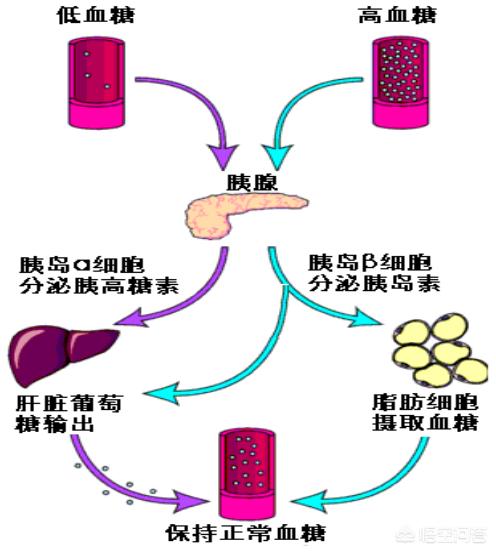

Le diabète est une maladie qui survient lorsque les cellules pancréatiques productrices d'insuline sont endommagées et meurent, produisant moins d'insuline pour transporter plus de sucre dans les cellules afin qu'il soit utilisé, ce qui entraîne une augmentation constante du taux de sucre dans le sang. Ce processus ne se produit pas en un court laps de temps, mais il s'agit plutôt d'une progression graduelle qui peut prendre des années ou plus.

La glycémie est la quantité de glucose dans le sang. Lorsque la glycémie est élevée à un certain niveau et que cet état persiste, le sang présente également un état hypertonique, de sorte qu'il existe une forte pression osmotique entre le sang et les tissus et cellules environnants, et que l'eau contenue dans les cellules continue de s'infiltrer dans la circulation sanguine, ce qui envoie un signal au cerveau concernant le manque d'eau, de sorte que le patient ressent la soif et a besoin de boire beaucoup d'eau.

De même, lorsque le sang passe par les reins, une grande quantité de sucre dans le sang, sous l'effet de la pression osmotique, entraîne une plus grande quantité d'eau dans l'urine, ce qui conduit à une augmentation de la quantité d'urine ; plus le sucre dans le sang est élevé, plus cet état se manifeste, ce qui explique la polyurie.

En raison du manque d'insuline de l'organisme, le sucre sanguin n'est pas pleinement utilisé, les cellules des tissus manquent d'énergie et se manifestent constamment au cerveau pour l'aider à signaler, le cerveau donnera des instructions pour manger plus afin d'augmenter la teneur en glucose du sang pour répondre aux besoins de l'organisme, le patient sera montré à manger pas assez à manger toujours vouloir manger les symptômes.

Dans des circonstances normales, outre le transport du glucose sanguin dans les cellules en vue de son utilisation, l'insuline convertit également l'excès de glucose sanguin et le stockage des graisses dans le foie et sous-cutané. Lorsque la sécrétion d'insuline est insuffisante dans une certaine mesure, même le transport du glucose sanguin dans les cellules ne peut satisfaire la demande, sans parler de la conversion du glucose sanguin en vue de son stockage, l'organisme doit également décomposer les graisses pour compenser le manque de glucose sanguin qui ne peut pas être utilisé, de sorte que le poids corporel diminue progressivement et que l'on devient de plus en plus mince. Le poids corporel diminue donc progressivement et l'organisme devient de plus en plus mince.